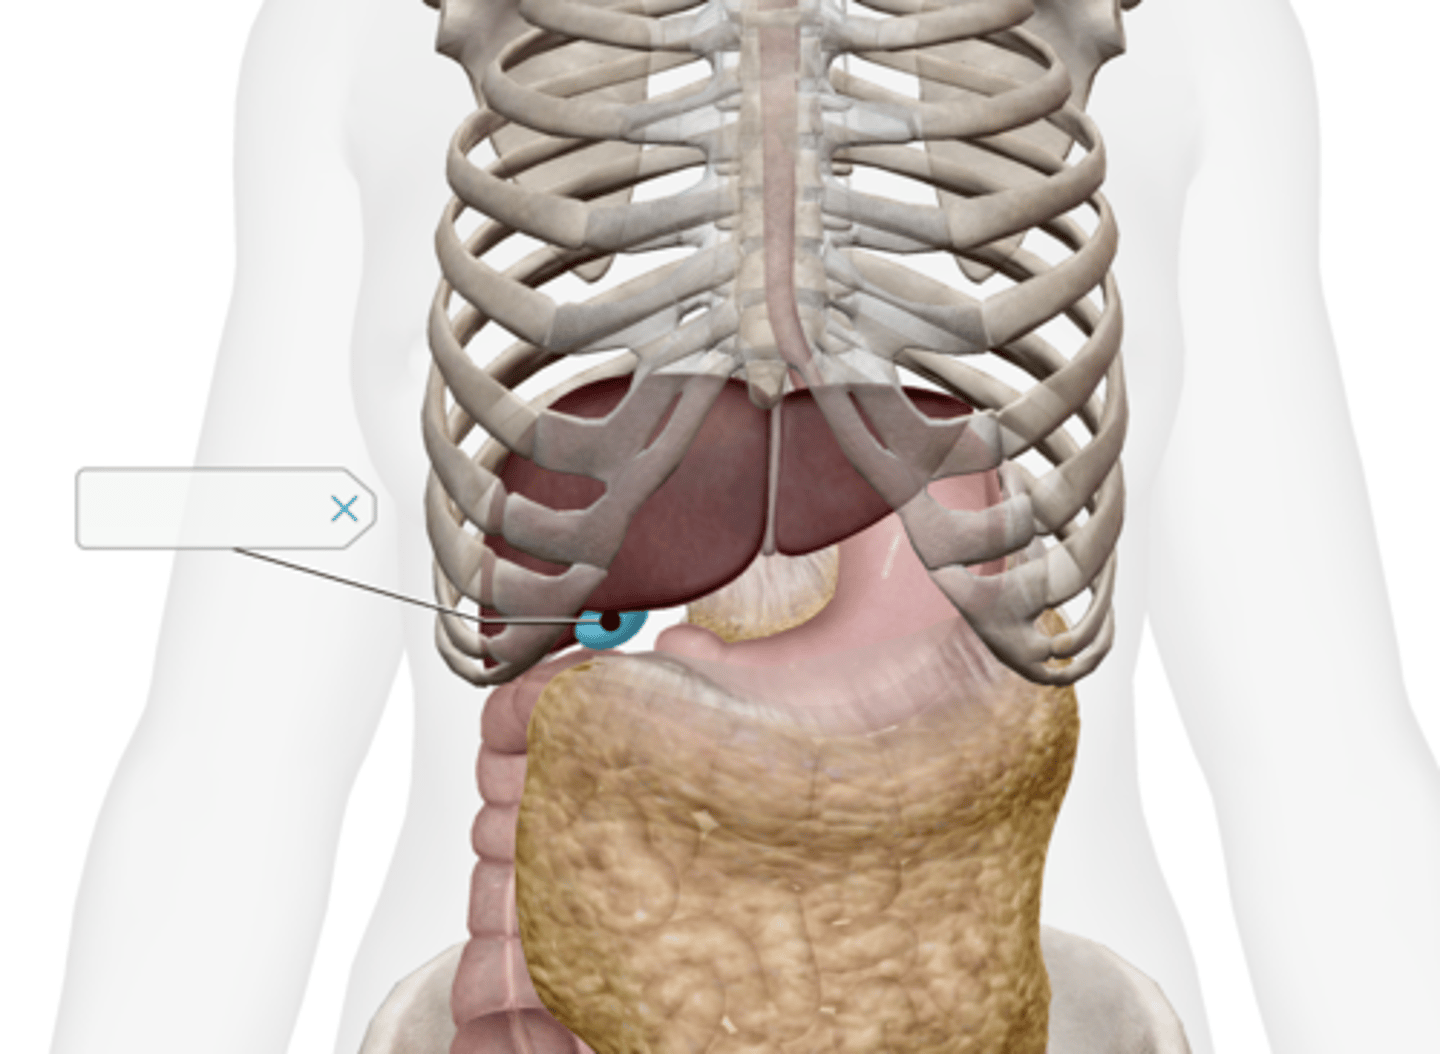

Gallbladder

Cystic duct

Common hepatic duct

Common bile duct